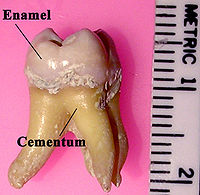

La couronne est recouverte d'émail, tissu minéralisé à plus de 97 %. Il est moins épais sur les dents temporaires. La racine est recouverte de cément, où s'enracinent les fibres collagèniques et élastiques du ligament alvéolo-dentaire ou desmodonte.